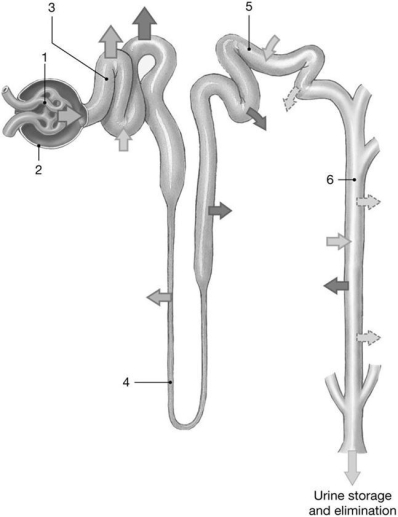

Figure 26-2 The Nephron

Use Figure 26-2 to answer the following questions:

-Which area is sensitive to aldosterone?